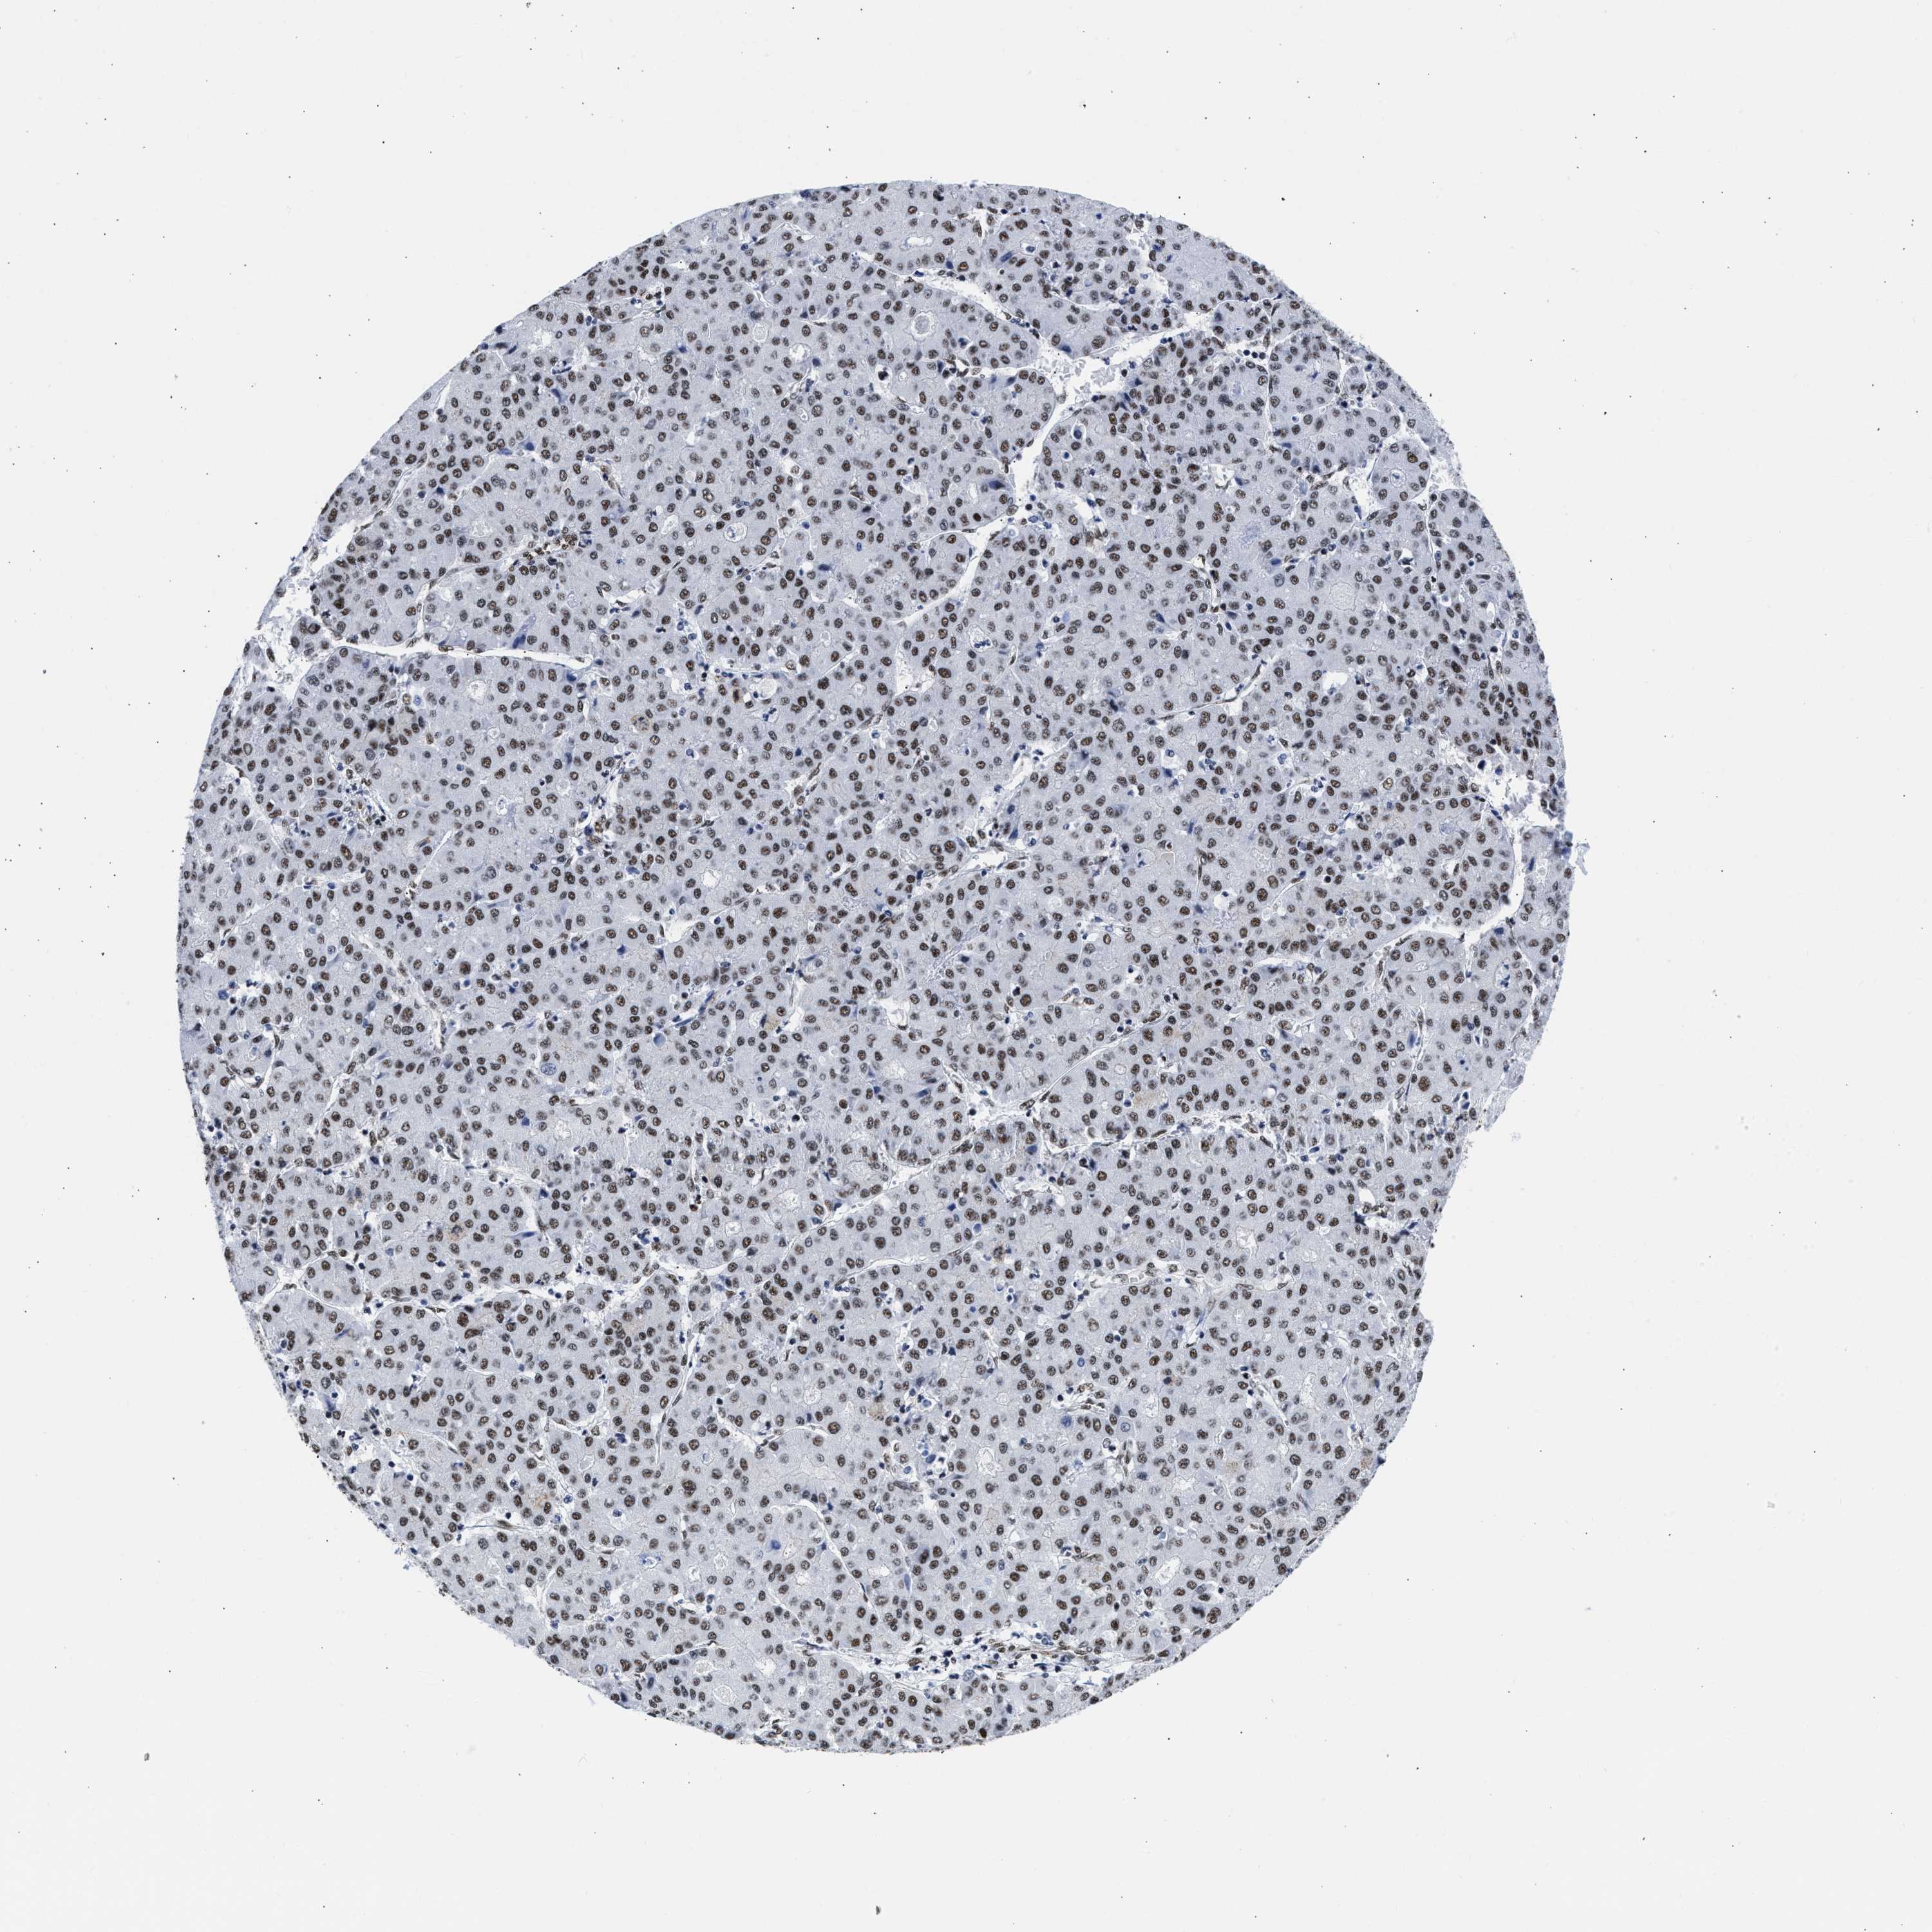

LIVER CANCER - Protein expressioni

A mouse-over function shows sample information and annotation data. Click on an image to view it in a full screen mode. Samples can be filtered based on level of antibody staining by selecting one or several of the following categories: high, medium, low and not detected. The assay and annotation is described here.

Note that samples used for immunohistochemistry by the Human Protein Atlas do not correspond to samples in the TCGA dataset.

Antibody stainingi

Antibody staining in the annotated cell types in the current human tissue is reported as not detected, low, medium, or high, based on conventional immunohistochemistry profiling in selected tissues. This score is based on the combination of the staining intensity and fraction of stained cells.

Each image is clickable and will lead to virtual microscopy that enables deeper exploration of all samples and also displays staining intensity scores, fraction scores and subcellular localization as well as patient and tissue information for each sample.

Antibody HPA018403

Staining

High

Medium

Low

Not detected

Intensity

Strong

Moderate

Weak

Negative

Quantity

>75%

75%-25%

<25%

None

Location

Nuclear

Cytoplasmic/membranous

Cytoplasmic/membranous,nuclear

Cholangiocarcinoma

Carcinoma, Hepatocellular, NOS